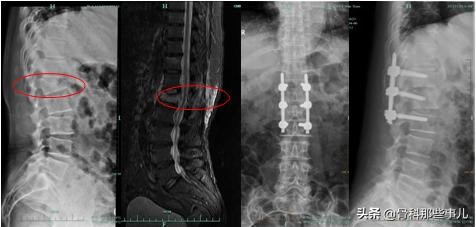

第一位是62岁的老太太,慢性腰痛很多年,自己也不是很在意。最近去菜场买菜的时候,弯腰拎起装菜的篮子,起身动作可能比较猛一些,然后就明显腰痛发作。在家撑了几天,疼痛实在不缓解才来医院检查,医生查体发现胸腰段有明显敲击痛,做检查发现多个腰椎压缩改变,其中有一节是新发的压缩性骨折。

多发椎体压缩改变,后凸畸形,第9胸椎骨质水肿,提示新鲜骨折

第二位是75岁的老先生,坐沙发的时候动作大了一些,结果出现腰痛。3天后到医院做检查,显示第12胸椎新发的压缩性骨折。

T1加权像,正常椎体的颜色是浅色的,黑色的第12胸椎提示新鲜骨折

4,最后一种特殊的情况,如果受伤很严重,碎骨块挤压到了周围的神经,出现了神经症状,比如说大小便障碍,这种情况保守治疗和微创手术都是不够的,需要做开放手术,把压到神经的骨头移开,然后使用钢钉对骨折的椎体进行固定。好在,这种情形非常少见。